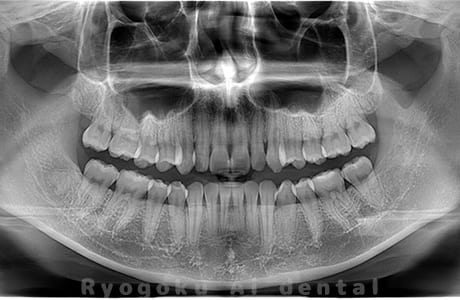

真っ直ぐ生えている親知らず

親知らずが真っ直ぐ生えているタイプです。

このタイプは真っ直ぐ生えていて咬み合わせに問題がなければ、抜歯しないケースもあります。ただし、虫歯になっていたり、痛みがあったり、咬み合わせが悪かったりすると抜歯をおすすめします。